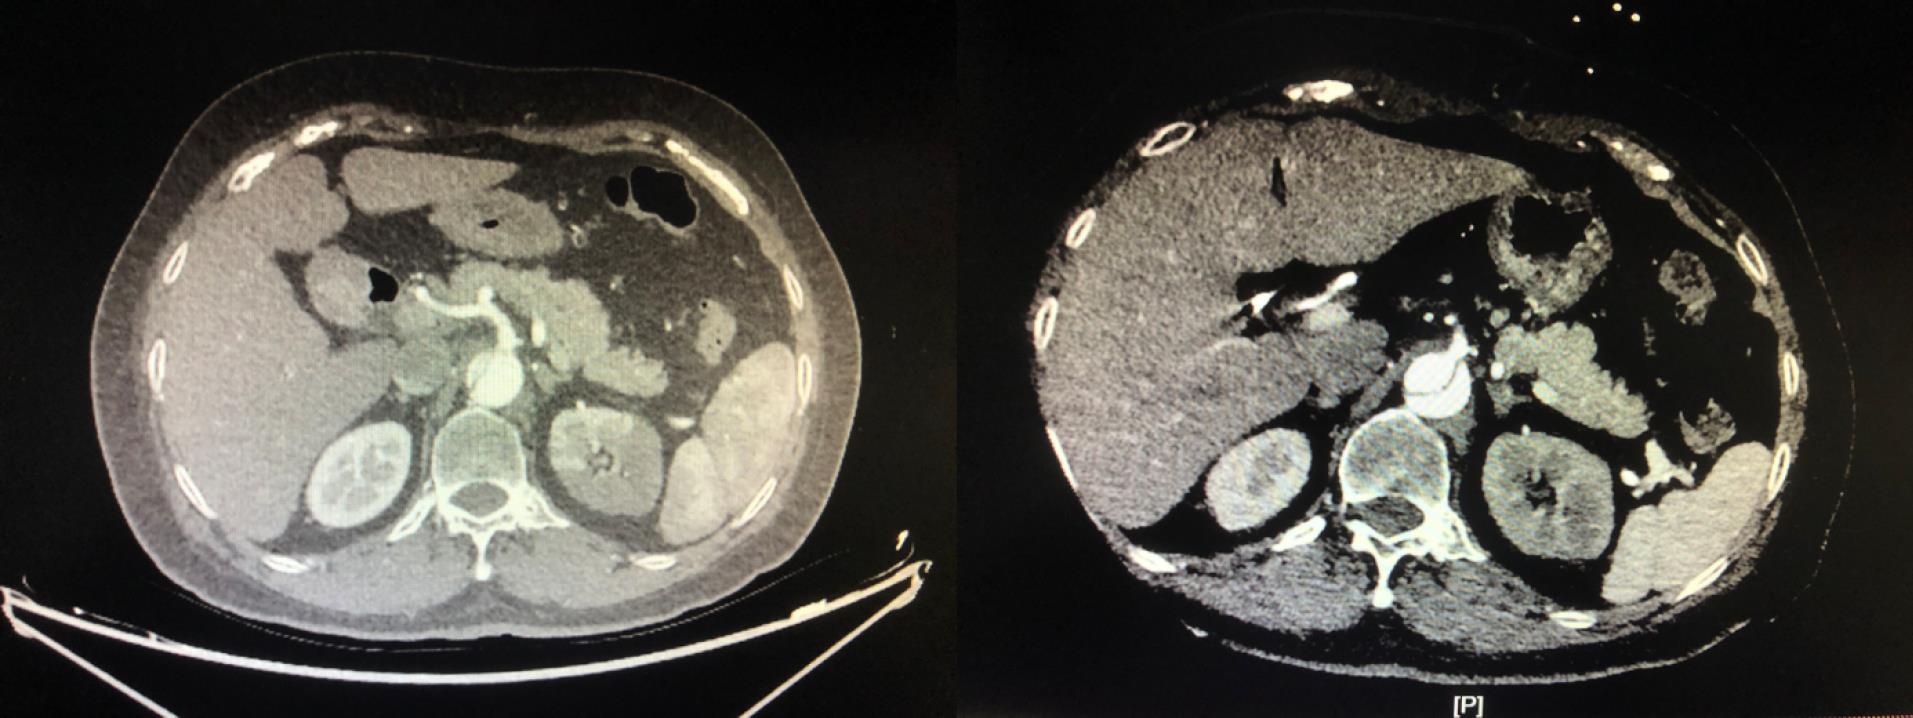

Multivariable logistic regression analysis showed that the perfusion method was significantly correlated with postoperative MFLA ratio. The postoperative MFLA ratio on the descending thoracic aorta were reduced more in PCC group than that in PC group with 0.35 ± 0.11 and 0.44 ± 0.13, respectively (Figure 3, P < 0.001). Moreover, postoperative involvement of the ostium of the dissected branch arteries on CTA including coeliac trunk artery, superior mesenteric artery, renal artery and Iliac artery was notably decreased in PCC group (Figure 4). There were a lower incidence rate of hepatic dysfunction and RRT in PCC group compared with those in PC group (15.5% vs. 39.8%, P < 0.001; 10.3% vs. 20.5%, P = 0.012, respectively). There was also a lower serum inflammation response (hs-CRP and IL-6) and anaerobic metabolism (lactate) in 24 hours after procedure in PCC group than those in PC group. The in-hospital survival, the duration of ICU and hospital stay was similar, but APACHE II score and mechanical ventilation time was lower in PCC than that in PC group, respectively (Table 3).

Figure 4.

The effect on the ostium of coeliac trunk artery by PCC technique. The preoperative image indicated that the ostium was almost involved by false lumen (left column). The postoperative image indicated that the ostium was totally stemmed from true lumen (right column). PCC: peripheral-to-centric cannulation